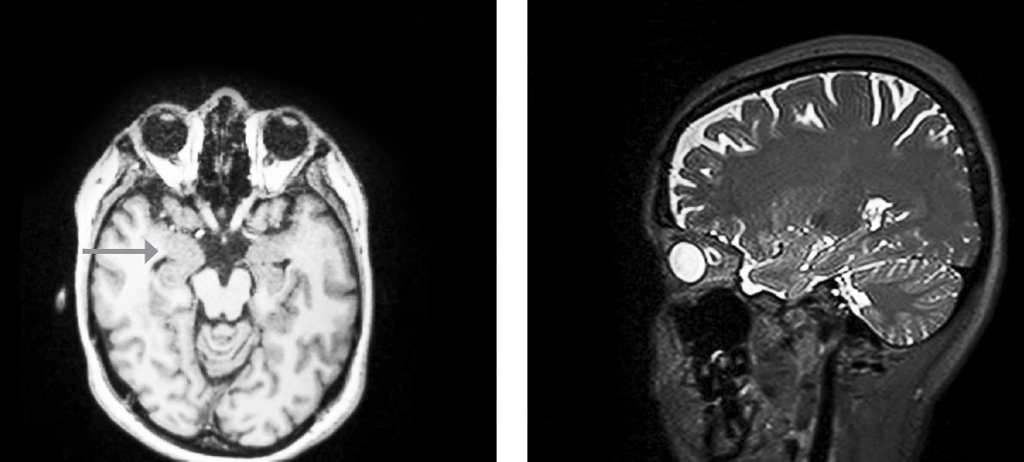

В декабре 2022 г. выполнила магнитно-резонансную томографию (МРТ) головного мозга: участок структурных изменений в кортикальных-субкортикальных медиобазальных отделах правой височной доли — более вероятно диэмбриопластическая нейроэпителиальная опухоль (DNET). Единичный очаг глиоза в левой и правой височных долях (рис. 1).

Рис. 1. Участок структурных изменений в кортикальных-субкортикальных медиобазальных отделах правой височной доли — более вероятна DNET. Единичный очаг глиоза в левой височной доле, вероятно, неспецифического резидуального генеза, не выраженного расширения наружного ликворного пространства. В сравнении с МРТ от 2009 г. — без динамики по размерам изменения в правой височной доле